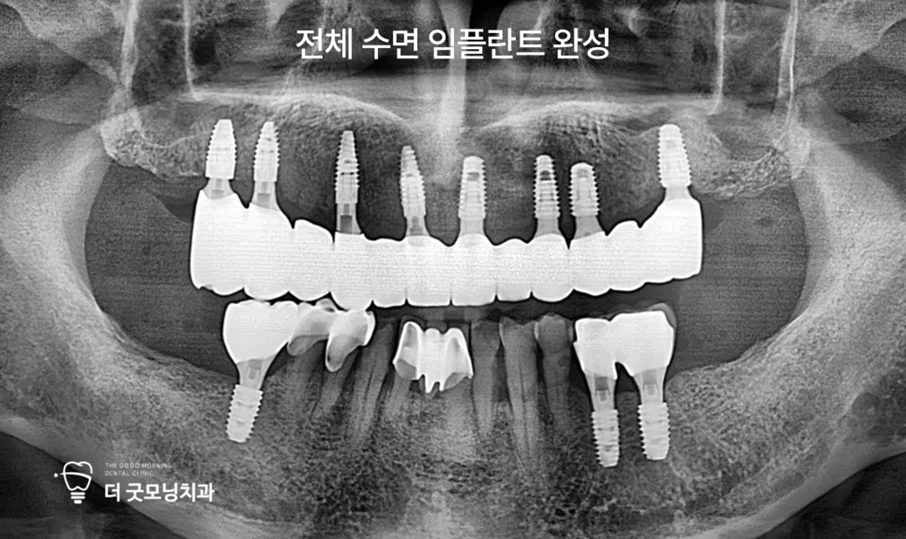

Step 7. 최종 보철 완성

임시 치아를 사용하며 약 3개월간 회복 단계를 거친 후, 충분한 고정력을 확인하고 최종 보철물을 장착하여 수면 전체 임플란트를 완성했습니다.

최종 결과 — 치료 전후 비교

치료 기간을 전략적으로 나누고 보험을 적극 활용함으로써, 총 11개 중 8개의 임플란트를 보험으로 처리하여 경제적 부담을 크게 줄일 수 있었습니다.